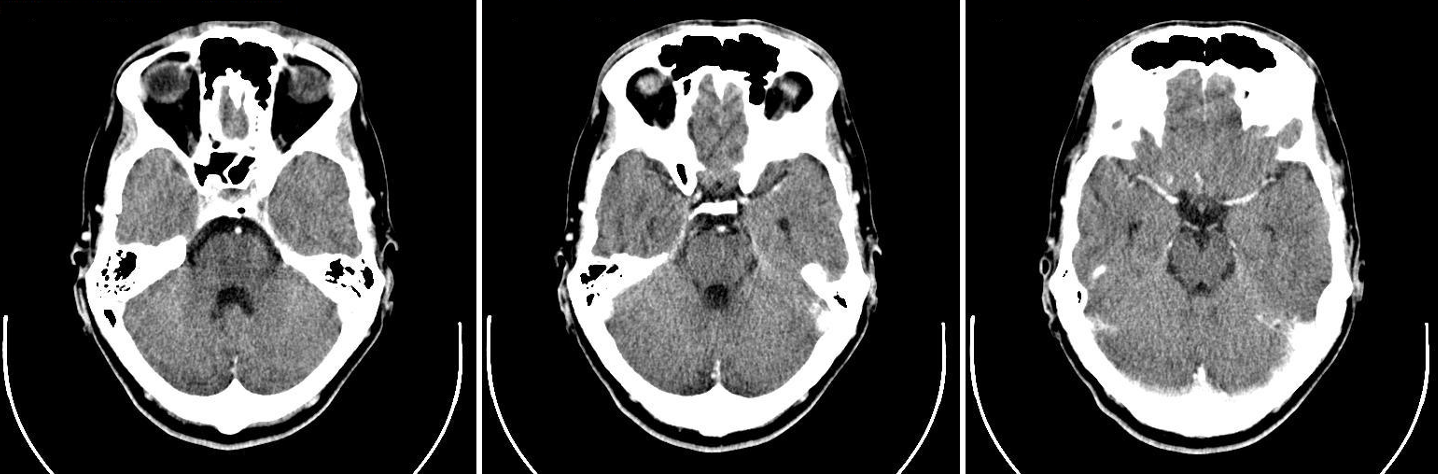

Figure 1: 2D slices of a human head from a CT scan.

Figure 1 contains brain CT images taken at different “horizontal” slices through the patient. In the images in Figure 1 the slices follow planes perpendicular to the foot-to-head direction. Each grayscale image is interpreted as a contour plot of the function \(\mu(x,y,z_0)\) in the plane \(z=z_0\).

Now we know what we are looking at in Figure 1, but we are not able to access these images (slices) directly. Instead, we take X-ray measurements outside the patient, and the goal is to determine the internal attenuation coefficient from external measurements by solving an inverse problem.